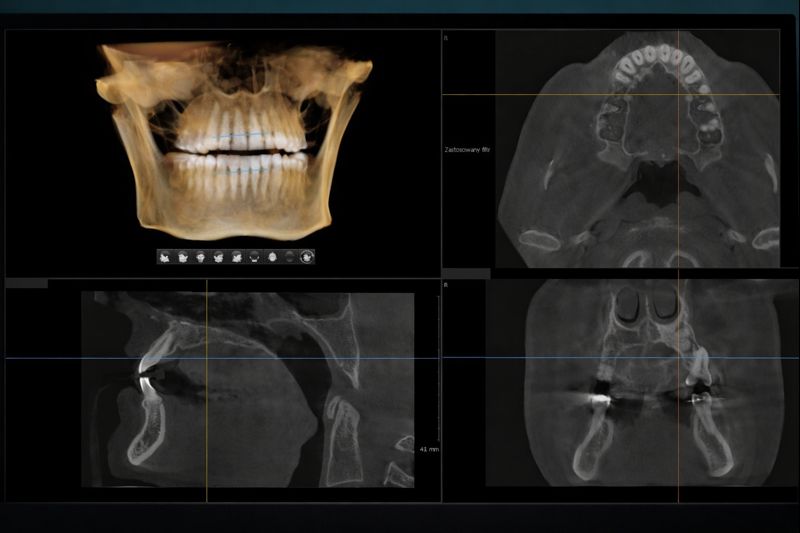

CBCT (Cone Beam Computed Tomography) je savremena metoda trodimenzionalnog snimanja zuba, vilice i okolnih struktura. Za razliku od klasičnog ortopan snimka koji daje ravnu, 2D sliku, CBCT pruža detaljan 3D prikaz koji stomatologu omogućava preciznu dijagnostiku i planiranje tretmana.

Koristi se u implantologiji, endodonciji, ortodonciji i oralnoj hirurgiji — svuda gde je potrebna preciznost koja prevazilazi ono što 2D snimak može da pokaže.

3D snimanje zuba obe vilice 12×9

- CBCT Standard (12×9 cm) obuhvata obe vilice u celosti — gornju i donju — u jednom skenu. Ovo je najsveobuhvatniji format 3D snimanja, namenjen situacijama kada je potrebna kompletna analiza: višestruki implantati, složene protetske rekonstrukcije, oralno-hirurška planiranja i ortodontska dijagnostika.